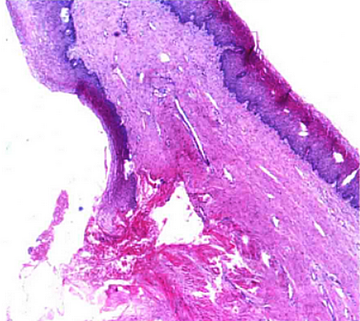

胚胎发育期间任何因素引起副中肾管的形成与融合异常,都会导致泌尿生殖窦发育成阴道的过程异常。按照阴道异常的临床表型来分,阴道发育异常分为MRKH综合征[a]、阴道部分闭锁、阴道横隔、阴道纵隔及阴道斜隔[9]阴道发育异常的临床表现多为闭经、痛经、性生活障碍等,[5]其中MRKH综合征病人多以原发性闭经及性生活困难为主诉;[4]阴道下段闭锁绝大多数病人至青春期发生周期性下腹坠痛,呈进行性加剧,[9]原发性闭经,婚后性交困难;阴道横隔大多数患者无月经影响,亦无症状,部分患者表现为原发性不孕,婚后出现性生活不满意,分娩时,出现产程受阻;[3]阴道斜隔综合征月经周期正常,均有痛经,部分患者有阴道分泌物呈脓性,有臭味。[9]

阴道发育异常主要依据临床表现、体格检查和妇科检查等进行诊断,[2]MRI可作为术前评估最有效的检查方法。[10]阴道发育异常治疗总的原则是解除梗阻、缓解痛经、尽量保留生育功能。[5]MRKH综合征,可采用阴道模具渐进式顶入的非手术方法或人工阴道成形术等手术治疗,[3]阴道闭锁阴道横隔、阴道纵隔和阴道斜隔综合征均建议手术治疗。[9]